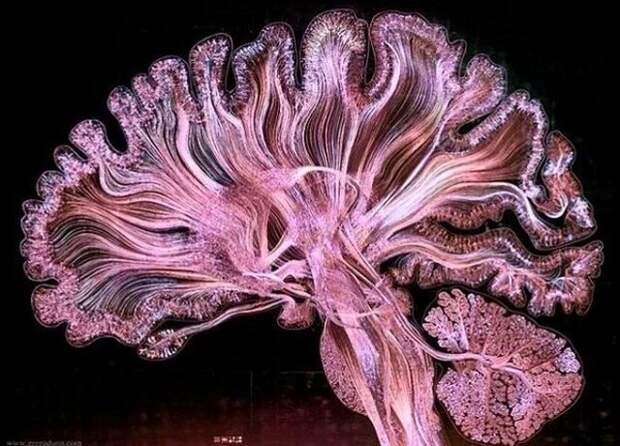

Нервные тракты, которые соединяют различные области мозга

Нервные тракты, которые соединяют различные области мозга  Рентген грудной клетки с аппаратом искусственного сердца